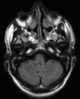

Epidemic encephalopathies

Transmissible spongiform encephalopathies (TSEs) are a group of progressive, invariably fatal, conditions that are associated with prions and affect the brain (encephalopathies) and nervous system of many animals, including humans, cattle, and sheep. According to the most widespread hypothesis, they are transmitted by prions, though some other data suggest an involvement of a Spiroplasma infection. [Source: Wikipedia ]